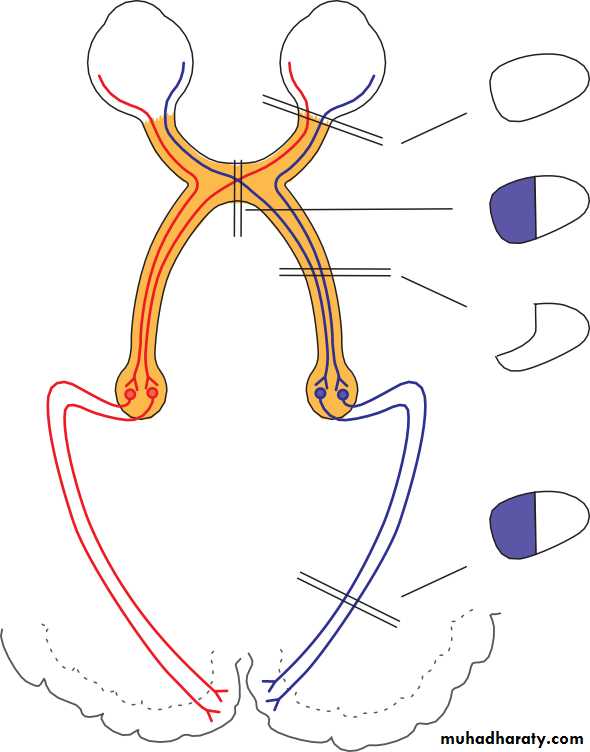

• In a patient in whom the pupil sizes are equal, the next step is to look for a defect in optic nerve function, using the ‘swinging flashlight test’. This is a sensitive index of an afferent conduction defect. The patient is seated in a dimly illuminated room and views a distant object. A torch is directed at each eye in turn while the pupils are observed. A unilateral defect in optic nerve conduction is demonstrated as a relative afferent pupil defect (RAPD) (see Fig. 2.4).

• TEST FOR RAPD

• Optic nerve damage• (a)

• Left eye

• Left eye• Right eye

• Right eye

• Optic nerve damage

• (b)

• Fig. 2.4 The relative afferent pupillary defect. The left optic nerve is damaged.

• (a) A light shone in the right eye causes both pupils to constrict. (b) When the light is moved to the left eye both pupils dilate because of the lack of afferent drive to the light reflex; a left relative afferent pupillary defect is present. Opacity of the ocular media (e.g. a dense cataract), or damage to the visual pathway beyond the lateral geniculate body will not cause a relative afferent pupillary defect.• Anatomical examination of the eye